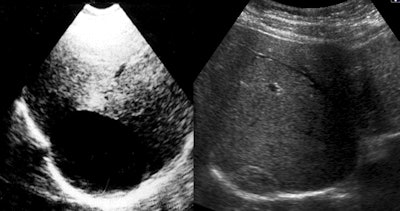

Ultrasound shows a liver CE 1 on the right side before the procedure in 1991 and a solid remnant with "pseudotumor appearance" -- 23 years after treatment. Images courtesy of Dr. Okan Akhan.

Ultrasound shows a liver CE 1 on the right side before the procedure in 1991 and a solid remnant with "pseudotumor appearance" -- 23 years after treatment. Images courtesy of Dr. Okan Akhan.Following on from their experimental study in sheep using a catheterization technique with hypertonic saline and alcohol, the Ankara group worked on a nonsurgical modified catheterization technique (MoCaT) based on complete evacuation of all cyst content, including the generated membrane and daughter vesicles, namely the fluid and the solid parts of the cyst. MoCaT, first described in 2007, has generated good results and low recurrence rates.